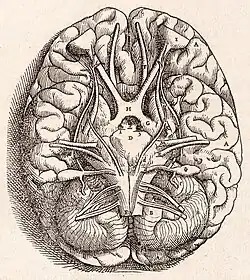

Анатомия мозжечка человека

А. Средний мозг

B. Варолиев мост

С. Продолговатый мозг

D. Спинной мозг

Е. Четвёртый желудочек

F. «древо жизни» мозжечка

G. Миндалина мозжечка

H. Передняя доля мозжечка

I. Задняя доля мозжечка

Особенностью мозжечка человека является то, что он, так же, как и головной мозг, состоит из правого и левого полушарий (лат. hemispheria cerebelli) и соединяющей их непарной структуры — «червя» (лат. vermis cerebelli). Мозжечок занимает почти всю заднюю черепную ямку. Поперечник мозжечка (9-10 см) значительно больше его переднезаднего размера (3-4 см)[19].